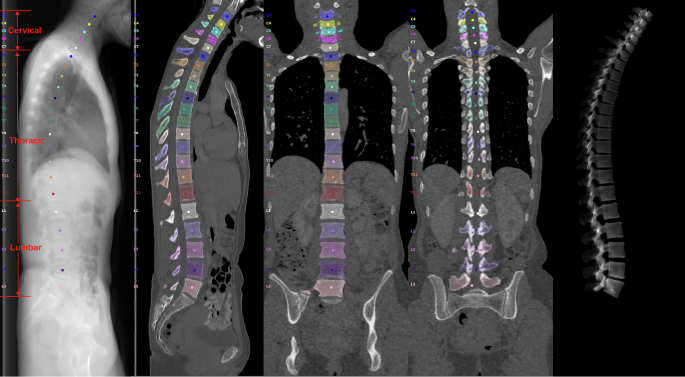

The diversity of MultiSpine is illustrated in Fig. 4, which shows a t-SNE projection of latent features extracted from the VertebraFormer encoder backbone (initialized with pre-trained weights). Distinct clusters corresponding to different anatomical regions and datasets indicate clear inter-domain shifts in style, contrast, and spatial structure. Representative axial CT slices from cervical, thoracic, and lumbar regions are shown in Fig. 5, highlighting anatomical differences that challenge cross-domain generalization.

Each color denotes a distinct anatomical region.

(Left Section) The colour-coded sagittal image presents the main three spinal regions: Cervical spine (C1-C7, marked in Red), thoracic spine (T1-T12, marked in Green) and Lumbar spine (L1-L5, marked in Blue). This image represents the anatomical structures associated with each spinal area, and provides a reference for the anatomical relationship between each spinal region. (Right Section) To demonstrate how each vertebra corresponds to the other, axial CT (cross-sectional) images of each spinal area are presented, using CT panels or slices to represent each region in 3 different rows.